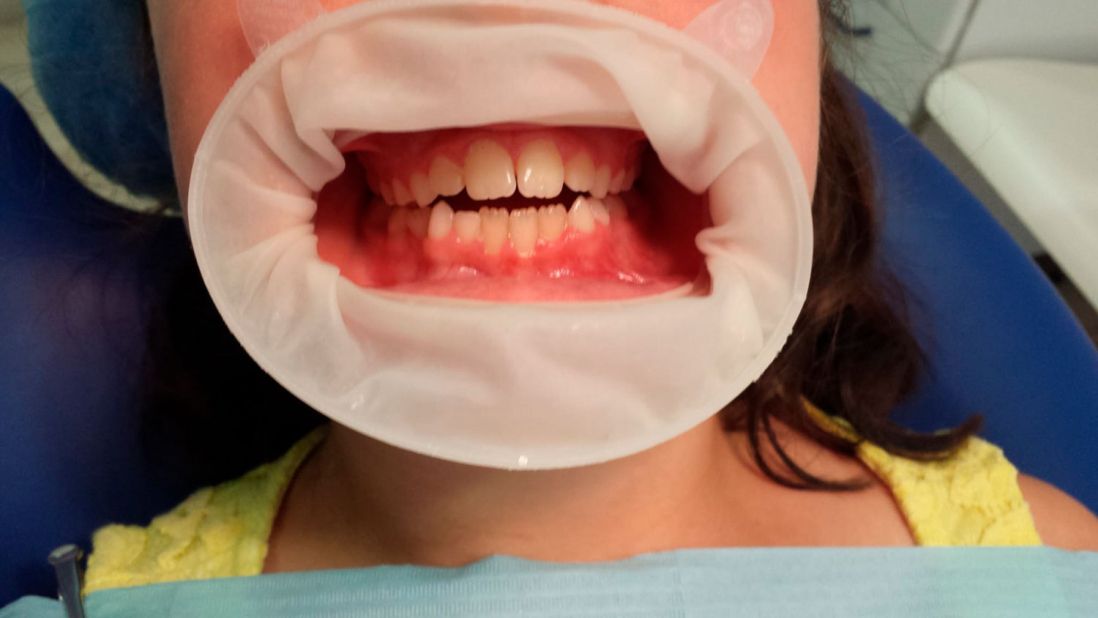

Ortopedia ortodoncia transposición